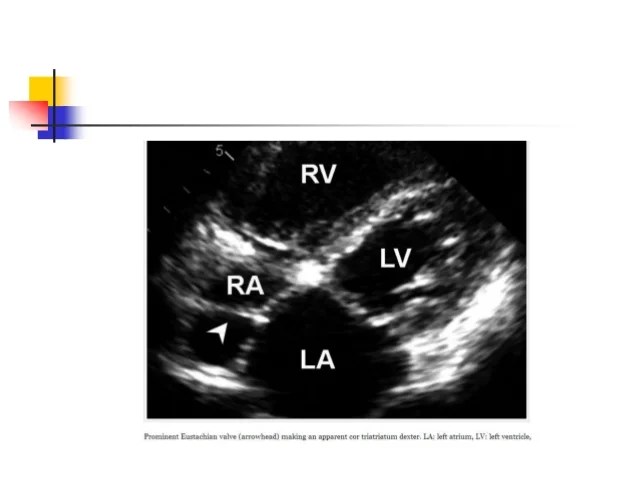

It is often noticed as fenestrated membranous structure or reticular network like structure in. Chiari's network (cn) is an embryologic remnant of eustachian valve located in the right atrium (ra). [the eustachian valve, the thebesian valve and the chiari network] [the eustachian valve, the thebesian valve and the chiari network] rev esp cardiol.

Chiari's network (cn) is an embryologic remnant of eustachian valve located in the right atrium (ra). Two structures found rarely within the right atrium that may mimic pathology are the eustachian valve and the chiari network.the eustachian valve was initially described by eustachius in. Chiari network is thought to a variant of eustachian valve.